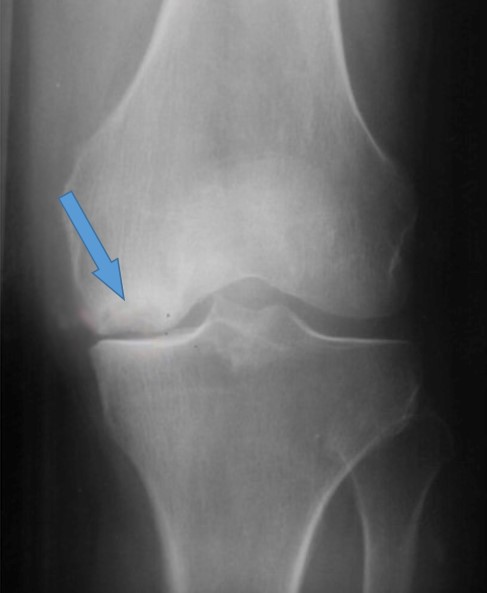

Высота суставной щели сохранена, но, присутствие остеофита, в совокупности с клиническими проявлениями, дает право ортопеду-травматологу поставить диагноз – гонартроз 1-2 стадии

Суставная щель сохранена, но неравномерна с медиальной и латеральной стороны. Четко визуализируется остеофит